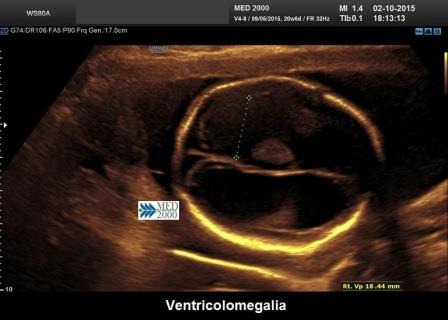

La diagnosi ecografica di ventricolomegalia (VM) si effettua misurando il diametro ventricolare a livello dell'atrio: il corretto posizionamento dei calipers è interno-interno alle pareti ventricolari a livello del glomo del plesso corioideo (Malinger G. et al., 2020).

La VM è caratterizzata da un diametro dell'atrio ventricolare, in scansione assiale, uguale o maggiore di 10 mm.; essa può essere distinta in tre forme (Vergani P. et al., 1998; Signorelli M.et al., 2004; Monteagudo A. et al., 2018):

- ventricolomegalia severa: il diametro dell'atrio supera i 15 mm. ed è associata ad Idrocefalia. (Melchiorre K et al., 2009)